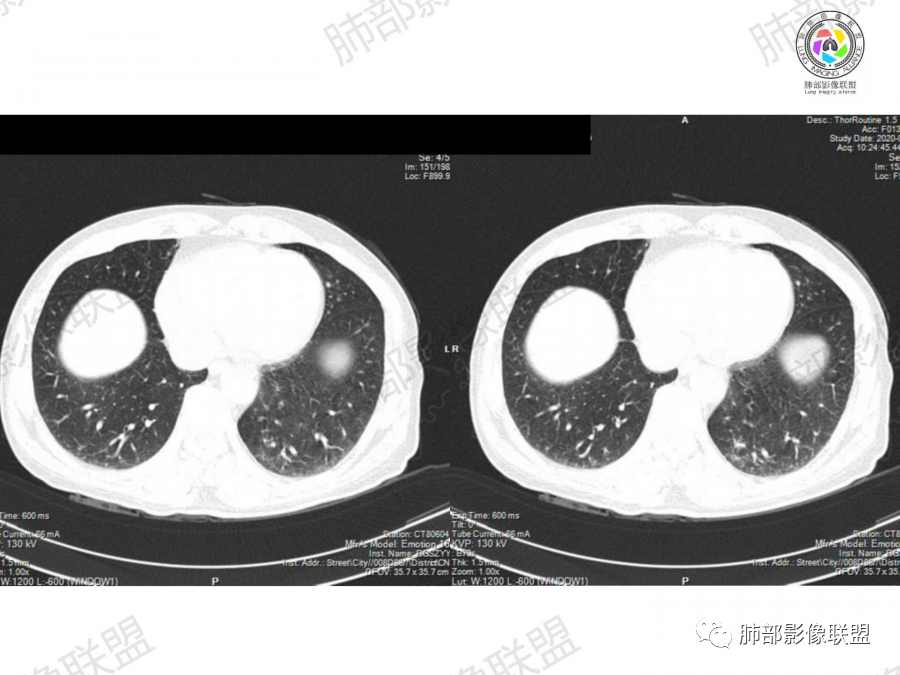

晨读,63岁男性,大量吸烟史,无症状,体检左下肺孤立结节,有分叶,棘突,疑似有血管穿行,考虑肺癌,腺癌?但部分平直,融合,鉴别隐球菌。

实性结节,短毛刺,分叶,腺癌?

鉴别:炎性肉芽肿(外缘平直,糊墙?)

晨读:左肺下叶胸膜下实性结节影边缘毛糙,有毛刺,分叶,近段支气管未见显示,可能堵塞,远端宽基底与胸膜相贴,边缘平直,部分彭隆,病灶局限、单发,无增强,不好判断肿瘤血供,临床男性,63岁,无症状,体检发现,有吸烟史,考虑恶性:腺癌,鳞癌,小细胞肺癌,鉴别:肺隐球菌建议增强及穿刺检查。

左肺下叶胸膜下结节,有膨隆有收缩,分叶毛刺,老年男性,首先考虑腺癌,鉴别炎性肉芽肿,常规治疗后复查。

晨读病例,老年人 ,吸烟史,左肺下叶结节影,密度均匀,边缘毛糙,周围可见长毛刺,病灶边缘分叶,局部膨隆,部分边界平直,收缩,病灶相邻胸膜处可见糊墙征象,病灶近肺门处见支气管堵塞,考虑恶性病变,周围型肺癌:鳞癌伴肺不张>腺癌,鉴别隐球,炎性假瘤。

细、长、软毛刺

边缘模糊,支气管关系不明确

糊墙,胸膜下脂肪间隙明显增厚

边缘平直为主,部分膨隆,糊墙征

密度比较均匀;

总体倾向炎性,不除外肿瘤。

2、影像表现:无肺气肿背景、定位左肺下叶后基底段,不规则结节、与支气管关系不明确,部分边缘平直、部分膨隆,病变与胸膜宽基底相连,病变与胸膜糊墙征,病变周围见细、长、软毛刺,病变密度比较均匀。影像总体倾向炎症、符合肺组织慢性炎症伴机化。